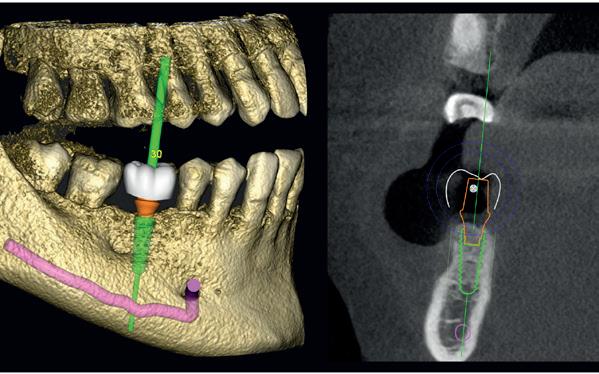

Voor het implantologisch onderzoek werd een CBCTscan (Trium CBCT, Acteon Frankrijk) vervaardigd van de edentate bovenkaak en in de software werd een planning gemaakt van 6 implantaten in de bovenkaak. De kaak kan opgedeeld worden in het front, tussen de 13 en 23 en de zijdelingse delen van de 14 t/m 17 en 24 t/m 27. Er dienen 2 implantaten in het front geplaatst te worden en 2 implantaten in de zijdelingse delen rechts en links, om een optimale verdeling van de implantaten (implant spread) te krijgen. De implantaten in deze casus werden gepland op posities 12, 22, 14, 24, 16 en 27. Tevens werd rekening gehouden met de krachtenverdeling óp de implantaten, deze zijn naar dorsaal toe forser dan in het front, daarom werd er gekozen voor brede implantaten (meer dan 5.0 mm in diameter) distaal en 4.0 mm diameter implantaten in het front. Voor de 16 was een crestale sinusbodemelevatie nodig en de 14 benodigde een kaakverbreding en verhoging.

Om de implantaten op de juiste vooraf geplande positie te implanteren, zijn er een aantal mogelijkheden (afbeelding 1 en 2). Eén daarvan is om de chirurgie guided uit te voeren, maar dat is lastig omdat de guide niet op elementen afgesteund kan worden. De guide dient dan met guide pins vastgeschroefd te worden, maar dat heeft als nadeel dat bij verplaatsing van de guide de implantaten niet op de juiste positie staan. Bij immediaat implanteren kan tegenwoordig gebruikgemaakt worden van meerdere stac-

1. Edentate maxilla

2. Planning in de CBCT-software Acteon AIS

kable guides, die op een base guide geklikt kunnen worden. Een tweede methode is om op basis van de CBCT-scan in de mond uit te meten waar de implantaat locaties zijn en door te kijken naar referentie van de onderkaak. In deze cases werd besloten om de implantaten vrij uit de hand te plaatsen.